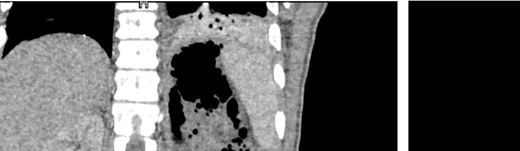

A 32-year-old male with no known medical history presented to the emergency department complaining of a high-grade fever of up to 40°C with rigors, intense hiccough, and back pain started four days prior. The patient reported a long-standing intravenous drug use (IVDU). Upon arrival, he was febrile (T: 41°C) and tachypneic (24 breaths/minute), the following vital signs were: heart rate 134 bpm, blood pressure 116/73 mmHg, oxygen saturation 94%. Examination of the abdomen revealed tenderness in the left iliac fossa and an abscess was observed in the left inguinofemoral region. Laboratory investigations revealed a leukocytosis of 12.300/mm3, elevated inflammatory markers (C-reactive protein of 19.24 mg/dl), and procalcitonin of 39 ng/ml, whereas the rest of the laboratory parameters were within normal limits. The microscopic urine analysis was normal. Blood cultures were obtained from separate venipuncture sites, and subsequently, we began intravenous fluid administration. Among the possible diagnoses, retroperitoneal abscess was prioritized due to clinical findings as well as because the patient reported several femoral vein punctures for drug injection. To set the diagnosis, the patient underwent a CT scan with IV and oral contrast. CT scan revealed swelling of the left femoral groin with the presence of a retroperitoneal abscess expanding through the left iliopsoas muscle to the perirenal space and left hemidiaphragm, which resulted in small left pleural effusion and infiltrates in the left lower lobe (Fig. 1).

CT images of the abdomen (venous phase) revealed a protruberance in the left inguinofemoral region extending into the retroperitoneal space, progressing as a perirenal abcess, spreading to the left sub-diaphragmatic region and causing an air-fluid level and an infiltrate in the lower lobe of the lung.